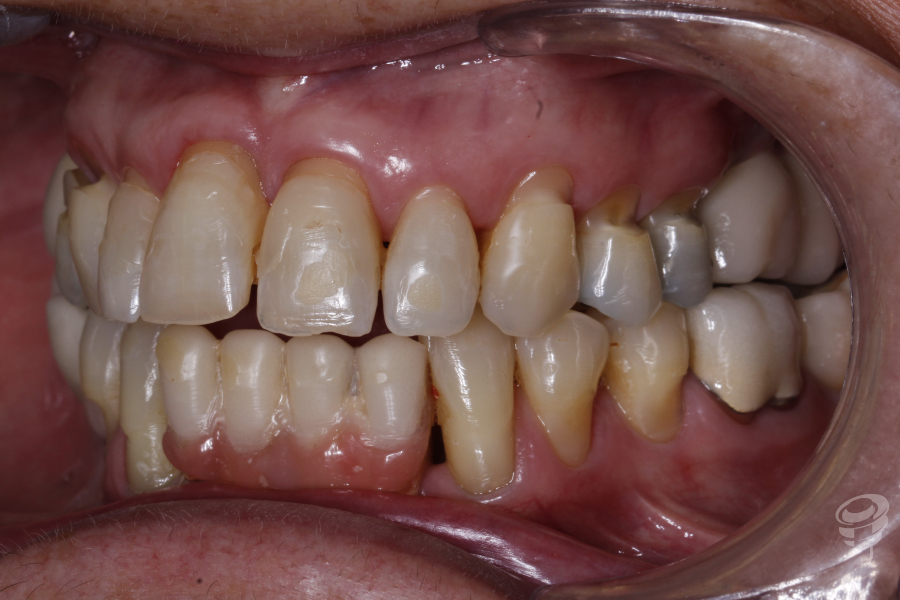

Podemos notar la pérdida de soporte periodontal que hay en el 11 y 21 y una descompensación asimétrica de los márgenes gingivales. Además, mordida abierta anterior y posterior derecha, mordida cruzada posterior bilateral, guías caninas ausentes. Un precario ajuste oclusal y bruxista. Podemos observar notables signos de abfracción en los cuellos 14, 13, 23, 24 y 25.

Figura 1

Figura 2

Figura 3

Figura 4